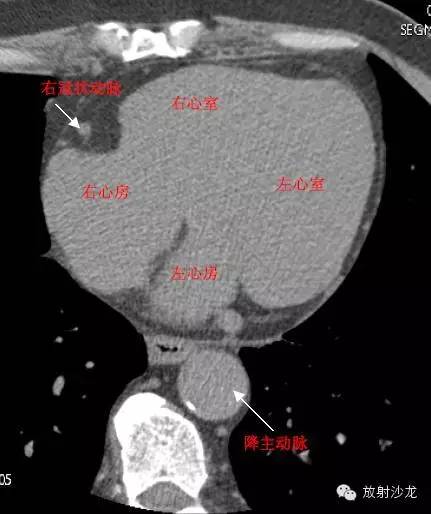

LA -Left Atrium左心房

RA -Right Atrium右心房

LV -Left Ventricle左心室

RV -Right Ventricle右心室

D. Aorta-Descending Aorta降主动脉

RCA -Right Coronary Artery 右冠状动脉